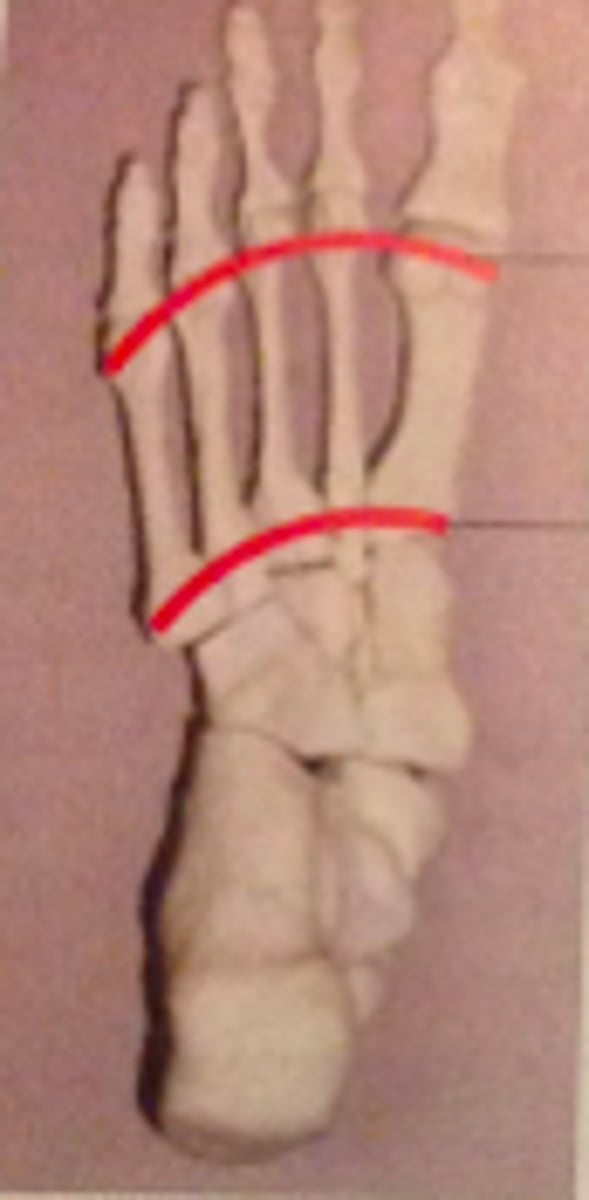

transverse arch

longitudinal arch